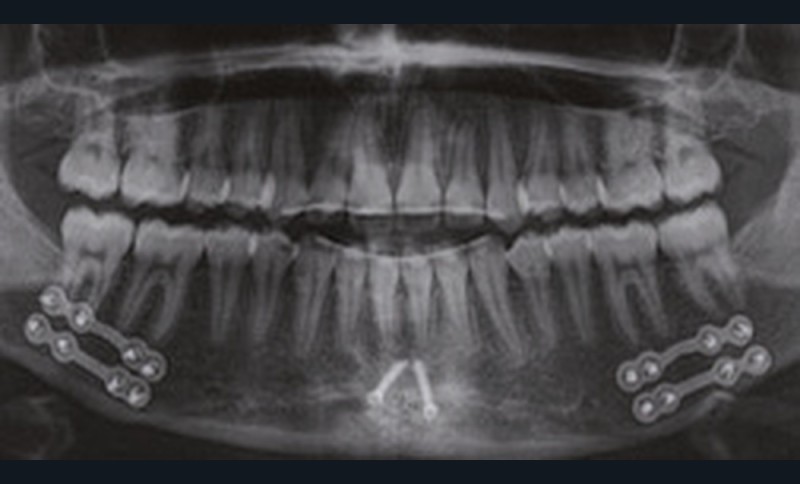

Nous équipons la patiente avec un appareil multi-attaches (.022 x .028 inch pré-informé Roth) mais nous n’avons pas activé l’arcade mandibulaire. La patiente est adressée au chirurgien maxillo-facial (Dr Gonzague Deffrennes, hôpital Beaujon) qui réalise l’avulsion des troisièmes molaires et la pose de plaques vissées avec émergence entre les premières et deuxièmes molaires mandibulaires dans l’axe des brackets (fig. 9). Étant donné l’absence d’encombrement au niveau incisif mandibulaire, nous pouvons rapidement mettre en place les tractions postérieures. Nous solidarisons ainsi le bloc antérieur de canine à canine et réalisons un recul en masse de l’arcade directement des canines aux plaques postérieures. La majeure partie du recul est faite sur un arc acier .018x.025 inch permettant le glissement. La force appliquée est de 250-300 g par côté.